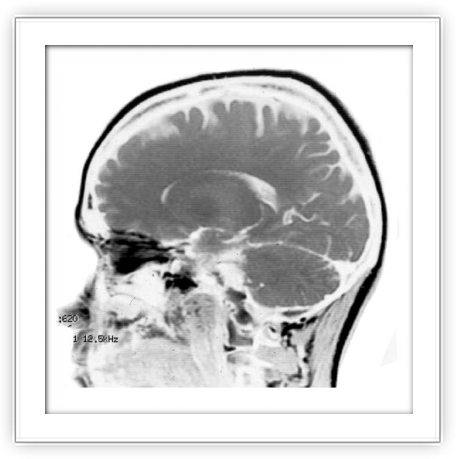

Neurología de la música y del lenguaje